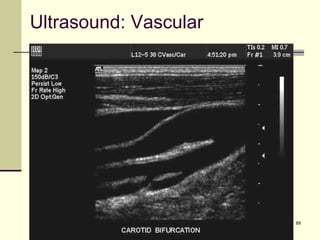

Ultrasound: Vascular

90